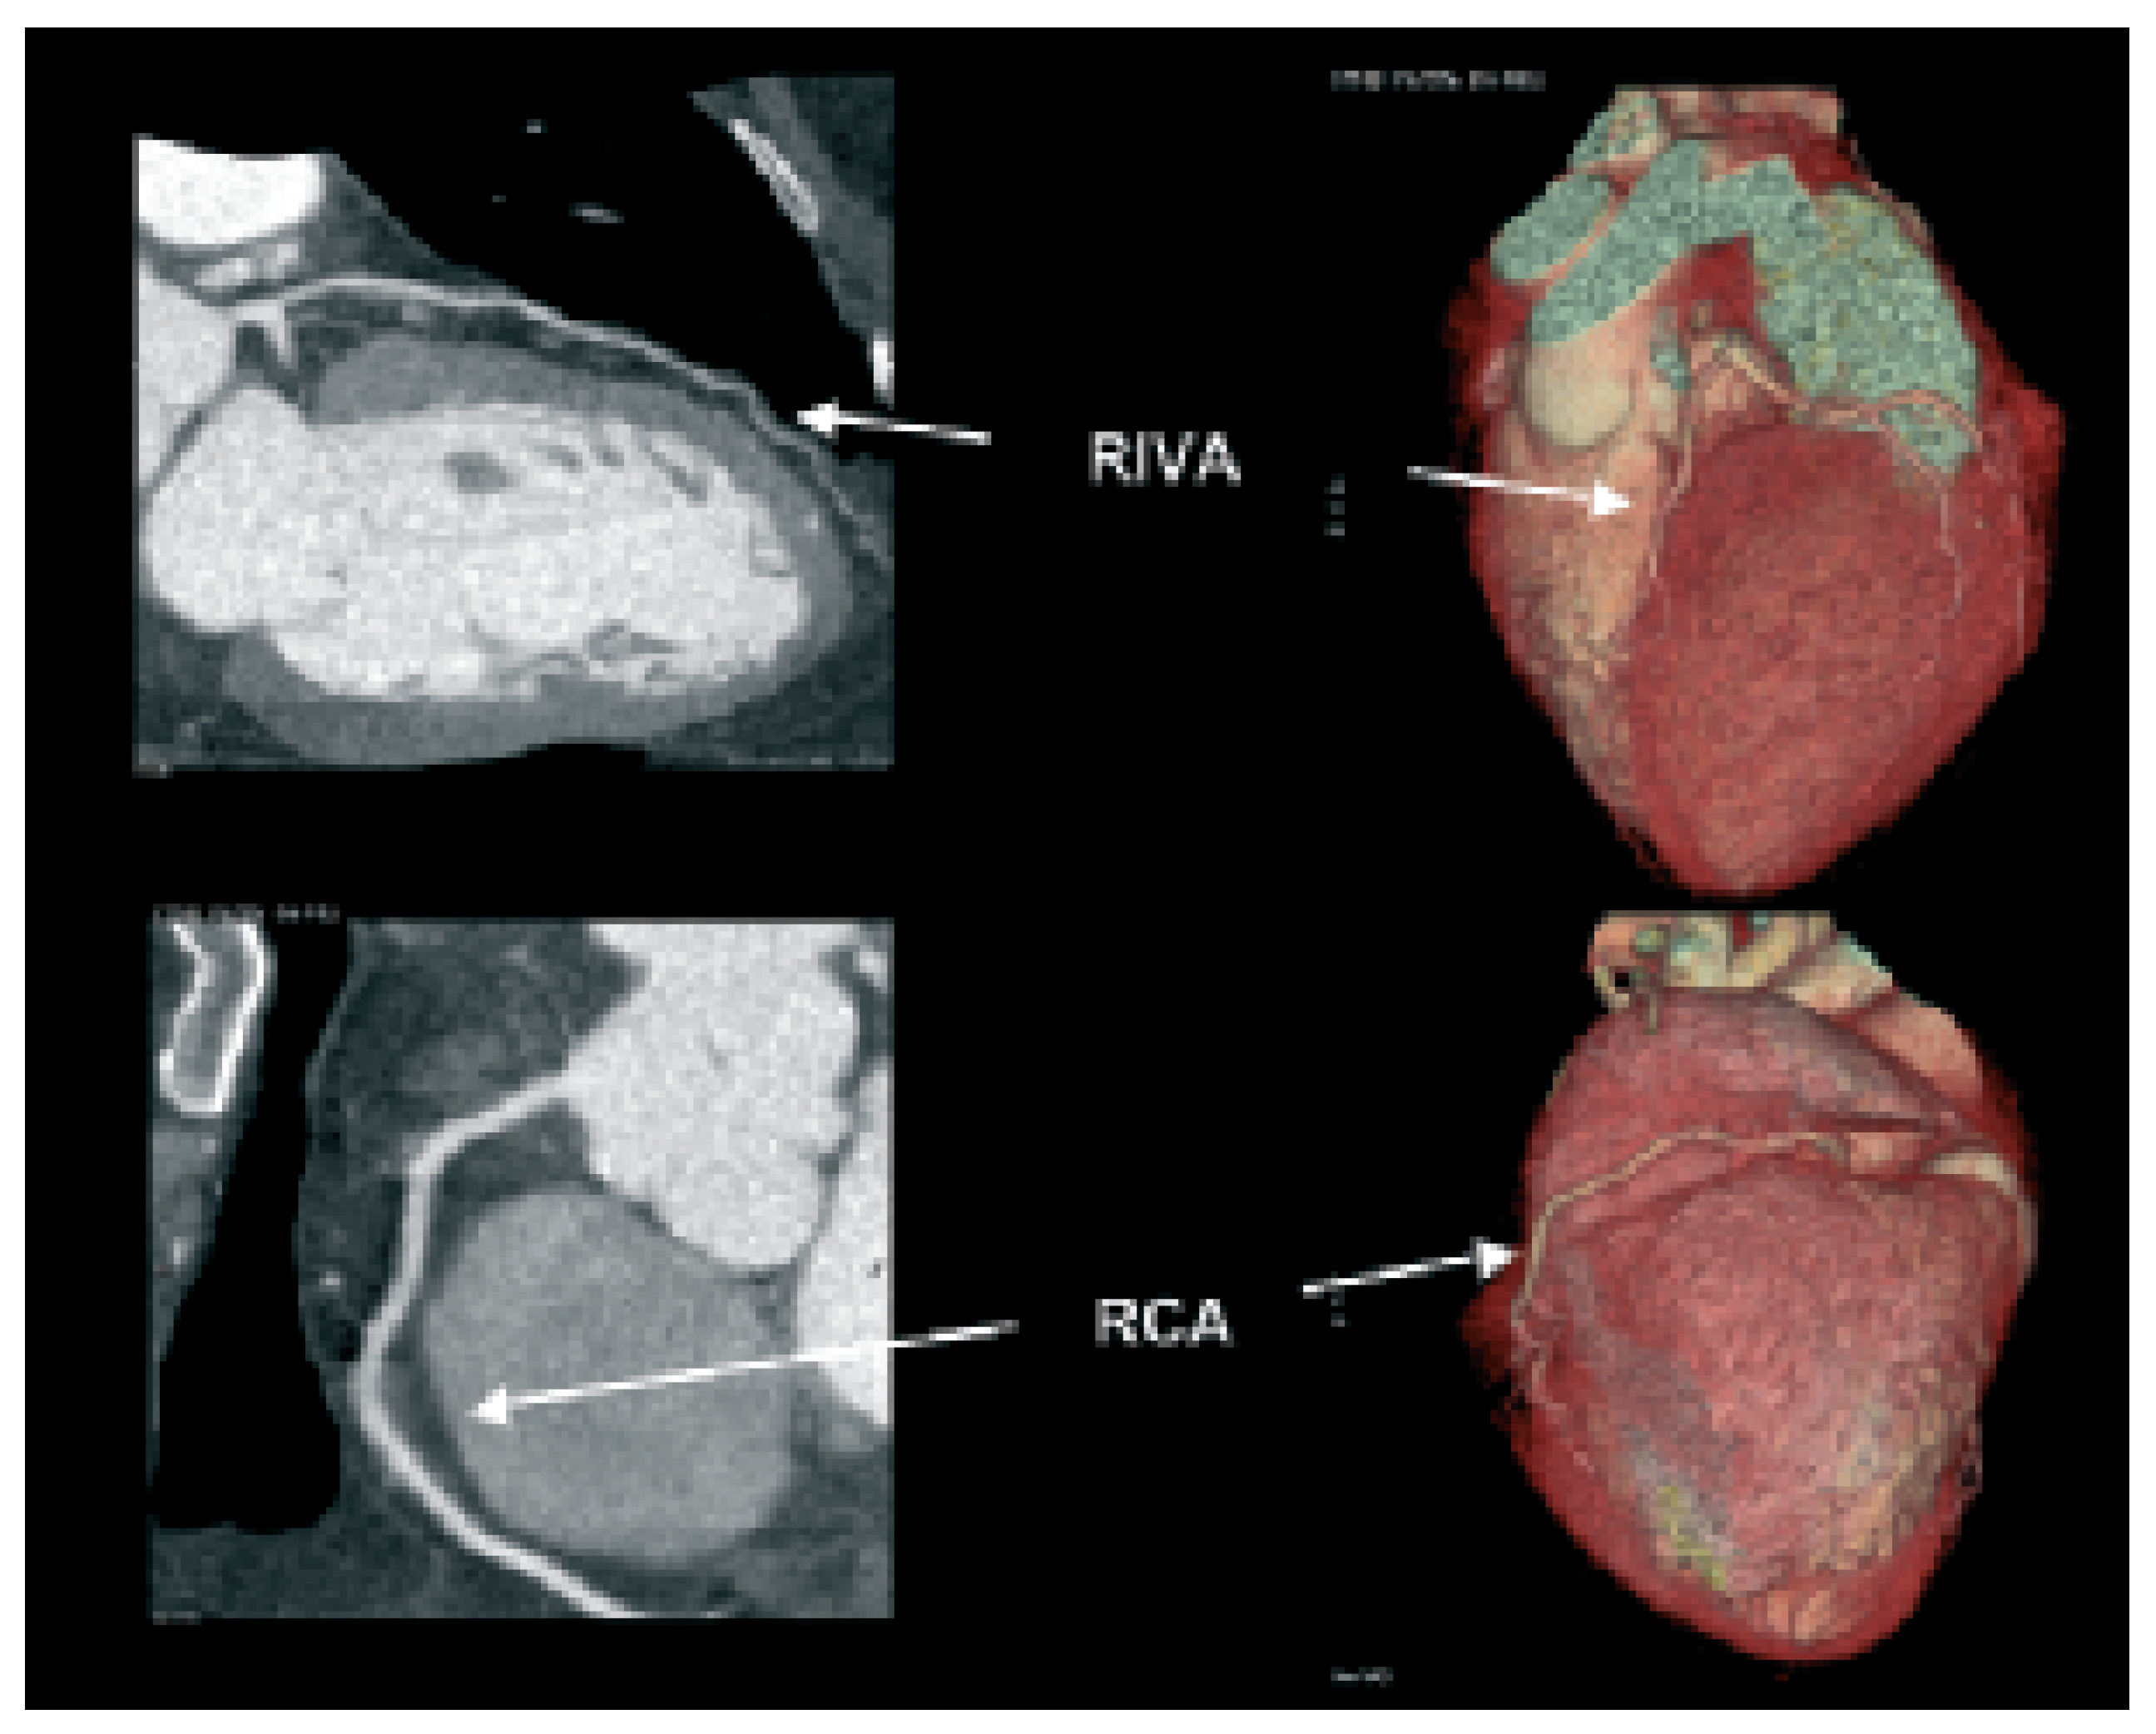

Abbildung 1. Darstellung von multiplanar rekonstruierten (MPR, links) und dreidimensionalen (3D-volume rendered) Bildern eines Patienten mit normalen Koronararterien. Ramus interventricularis anterior (RIVA) und rechte Koronararterie (RCA).

Durch die rasante Entwicklung immer schneller werdender Geräte, welche ursprünglich langsam Schicht um Schicht, bald aber 4, 16, 32 und seit kurzem bereits 64 Zeilen gleichzeitig erfassen, wurde es möglich, innert kürzester Zeit—allerdings mit erheblicher Strahlenbelastung—die Herzkranzgefässe mit bisher ungeahnter Genauigkeit darzustellen (Abb. 1; [6]). Die Herzkranzgefässe lassen sich hiermit in ihrer gesamten Länge neben dem kardialen Bereich vollständig verfolgen, Einengungen können in vielen Fällen erkannt werden. Zudem bietet die Computertomographie die Möglichkeit der Quantifizierung von Kalziumablagerungen in der Gefässwand, wie sie für die Arteriosklerose typisch sind («Gefässverkalkung»; [7]). Kalk ist Ausdruck des Ausmasses des arteriosklerotischen Prozesses. Entsprechend wurde von verschiedenen Forschungsgruppen ein eigentlicher Kalzium-Score entwickelt, welcher ähnlich wie die kardiovaskulären Risikofaktoren prognostische Hinweise liefern soll. Der prognostische Wert eines solchen Scores über die bereits verfügbaren Risikofaktorenanalyse hinaus (ESC Score Card u.a.m.), ist allerdings sehr fraglich und wird daher heute nur noch von wenigen Zentren verwendet.